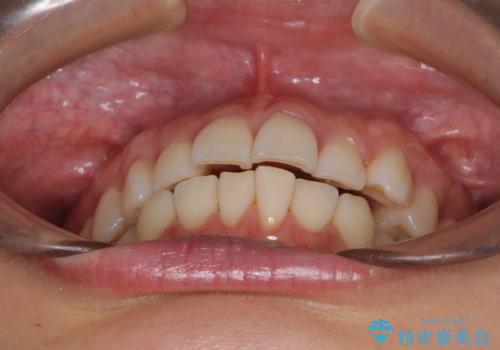

- 奥歯の咬み合わせと、上下前歯の隙間を気にして来院された患者様です。

上顎の歯列全体が、下顎歯列に対して前方に位置しており、その影響で上顎前歯がやや前方に突出している状態でした。

横顔の印象から、抜歯をして積極的に口元を引っ込める必要はなかったため、アンカースクリューを用いて上顎歯列全体を後方に移動させることとしました。

奥歯の咬み合わせは理想的な状態に改善され、その結果として上下歯列もバランスの良い位置に収めることができました。

若干ではあるものの上顎前歯を内側に移動させることができ、以前よりも口が閉じやすいと感じるようになりました。